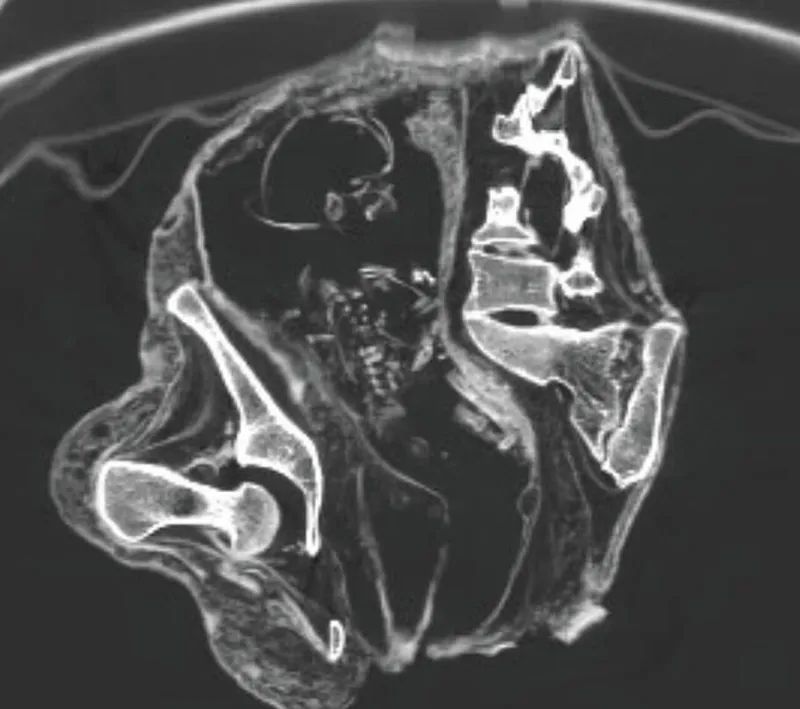

Как пишет Daily Mail, женщина, которую ученые прозвали Монтсеррат, умерла 1200 лет назад. Ученые решили сделать КТ из-за необычной позы, в которой она обхватывала живот руками.

"На снимках компьютерной томографии зафиксирован плод, лежащий на спине головой вниз, в районе живота и грудной клетки, а руки расположены ближе к тазовой области", – говорится в статье.